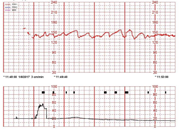

분만 기간 동안 산모의 자궁 수축 변화 양상 및 태아의 심음 등을 모니터링 하여 산모의 이상 진통이나 기타 이상을 관찰하는 검사인 태아 심박동 모니터링으로부터 획득한 데이터

태아 심박동 검사 모니터링 이미지를 통해 태아 상태 진단 분류 및 이상 시점 탐지를 위한 인공지능 학습용 데이터 구축

• 태아 심박동 모니터링 이미지 데이터

- 원천데이터(PNG)